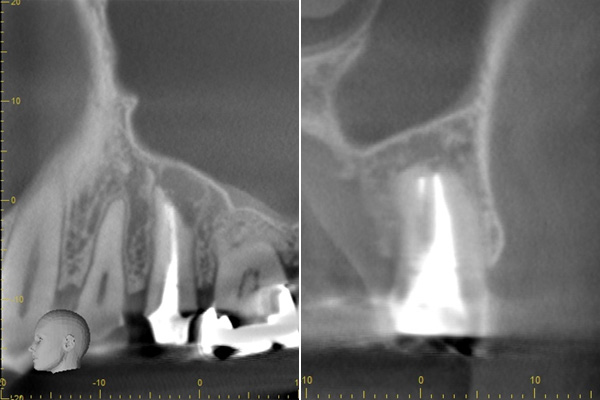

治療後、腫れの大きさの確認のためにCTを撮影すると、上顎洞にまでおよぶ大きな炎症があり、骨が大きくなくなっていることが確認できました。

基礎に忠実に根の中をしっかり清掃し、防腐剤を詰めて経過をみるために3ヶ月後に再度CTを撮影しました。以前とは比べ物にならないくらい、上顎洞の炎症はなくなり。上顎洞を隔てる骨の再生もできました。 またこの治療で一番良かったのは、治療しなければならない歯とそうでない歯を鑑別できたことです。手前の歯はやはり治療する必要がなかったのです。

初診終了後にCT撮影です。上顎洞と歯が連続してしまうくらい炎症が広がっています。